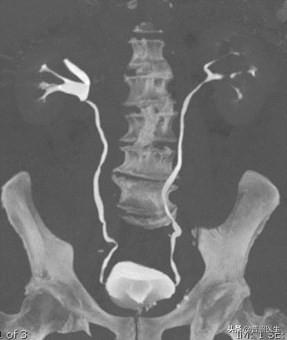

既要检查结石,又可以检查肾功能:CTU(CT尿路造影),通过给静脉注射造影剂,由肾脏排泄至尿路而使整个泌尿系显影,即可看见结石堵塞的位置。

含有造影剂的尿液会再CT下显影!